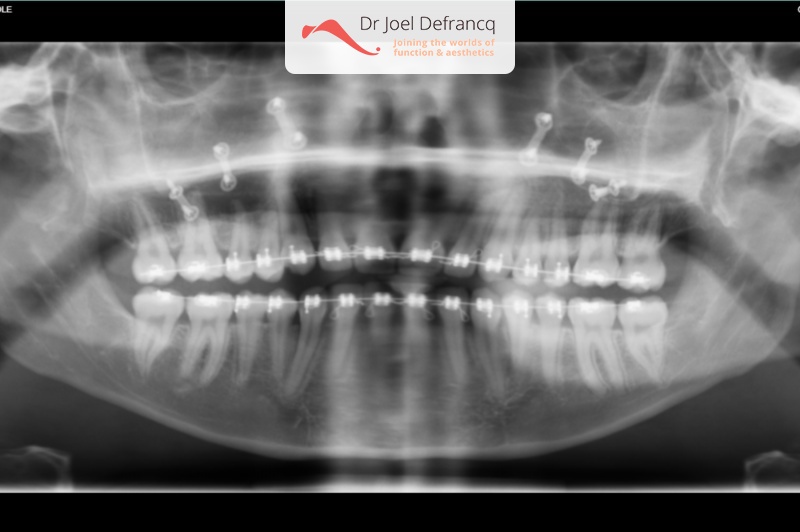

Daphne: Open beet

Diagnose van het gezicht

- Te lange bovenkaak

- Open beet

Dentale diagnose

- Klasse I

Kaakchirurgie

- Verlenging bovenkaak (Le Fort I)